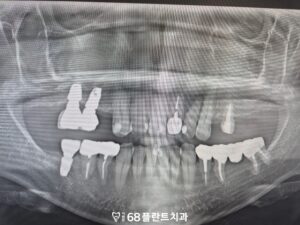

또한 임시치아로 보호하고 있던 치아 역시

최종 보철로 교체하여 마무리하였습니다.

◆ 전 > 후 ◆